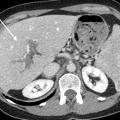

Thrombose porte et ischémie mésentérique veineuses

La thrombose de la veine porte (TVP) se caractérise par l’obstruction, le plus souvent par un thrombus, de la veine porte et/ou de ses branches portales (droite et/ou gauche). Cette obstruction peut être partielle ou complète, récente (moins de six mois) ou chronique (plus de six mois) et peut également affecter les vaisseaux…